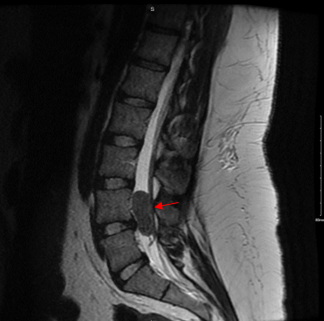

On examination, the patient demonstrated mild diffuse tenderness in the lumbar region. Neurologic exam including gait and reflexes was within normal limits. Given the chronicity of her symptoms, further imaging was indicated to evaluate for an underlying etiology of her pain. The patient underwent an MRI of the lumbar spine, which revealed a well-circumscribed mass noted in the spinal canal at the level of L4-L5. This mass occupied the entire spinal canal and compressed the adjacent neural structures. The lesion appeared intradural, and initial differential diagnosis included meningioma, schwannoma, ependymoma or other primary central nervous system (CNS) neoplasm. Additional cross-sectional imaging of the chest, abdomen, and pelvis did not show evidence of metastasis.